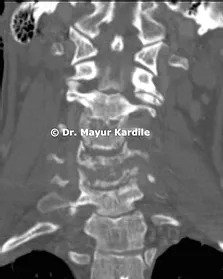

Her MRI revealed infection at C5 and C6 vertebral level with kyphosis

CT scan of the cervical spine revealed complete destruction and collapse of C5 and C6 vertebra with kyphosis deformity